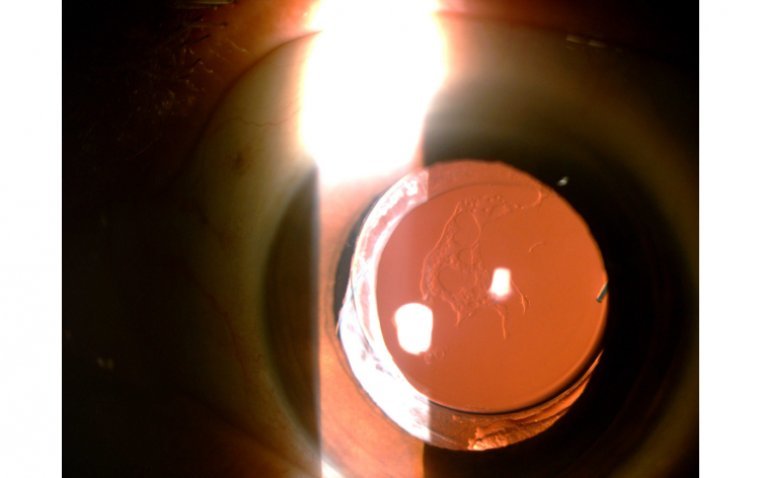

Posterior Capsular Opacification | OBN

What Is Post-Capsular Opacification? After a smooth sail through cataract surgery, post capsular opacification (PCO) can appear like a rogue wave, unexpected and potentially disruptive. It’s not an iceberg that sinks the ship, but it’s certainly worth keeping an eye…